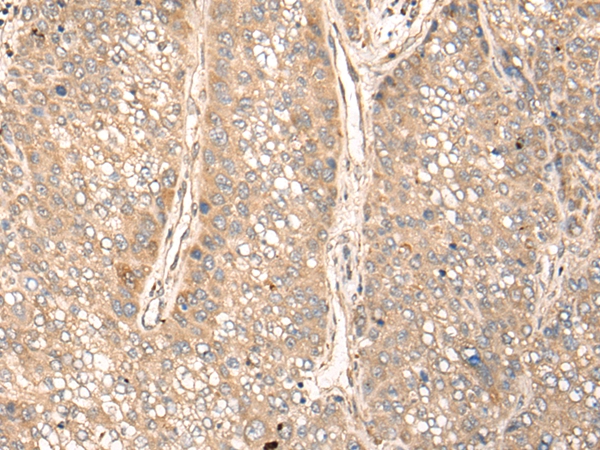

The image on the left is immunohistochemistry of paraffin-embedded Human liver cancer tissue using 46566(GPANK1 Antibody) at dilution 1/30, on the right is treated with fusion protein. (Original magnification: x200)